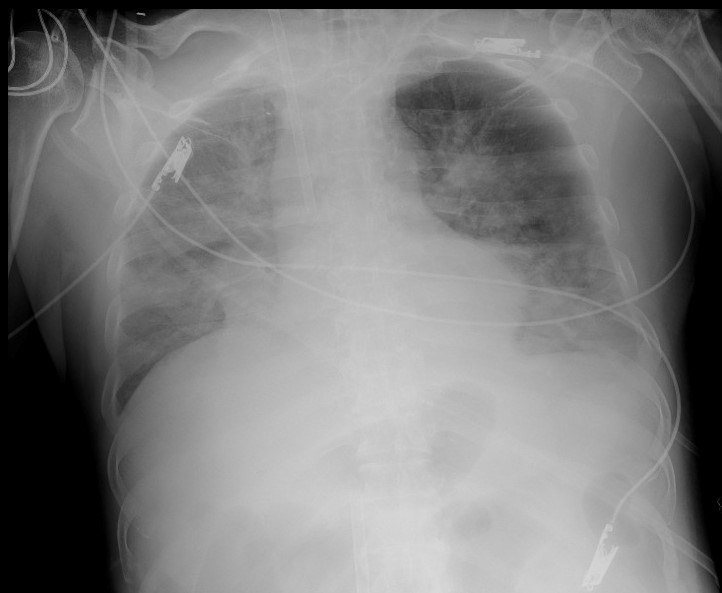

Bệnh nhân T. sốc nặng, suy hô hấp, phải duy trì vận mạch liều rất cao, thở máy nhưng phổi co thắt nhiều, máy thở không thể đẩy khí vào phổi để thông khí được.

Trực tiếp điều trị cho bệnh nhân, BS Nguyễn Bá Cường - Trung tâm Hồi sức tích cực, Bệnh viện Bạch Mai, cho biết, bệnh nhân được chuyển đến Bệnh viện Bạch Mai ngày 30/5 trong tình trạng suy hô hấp rất nặng, phổi không còn đảm bảo được chức năng thông khí ngay cả khi hỗ trợ máy thở tối đa. Bệnh nhân đã được vào ECMO và tiếp tục các biện pháp hồi sức tích cực: kháng sinh, kháng nấm, lọc máu, vận mạch…

Ngày 30/5, bệnh nhân được nội soi phế quản xuất hiện nhiều các mảng giả mạc thùy dưới phổi 2 bên. Với kinh nghiệm điều trị cho nhiều ca phức tạp, các bác sĩ đã nghĩ ngay đến nấm. Đến ngày 1/6, nội soi phế quản, bác sĩ thấy giả mạc phát triển trên toàn bộ niêm mạc đường thở tạo nên các đám sùi và các giả mạc đan xen nhau như mạng nhện, lấp kín hết lòng khí phế quản.

Ngày 2/6, kết quả nội soi cho thấy các giả mạc bám thành đường thở bong dần ra. Tất cả các mẫu bệnh phẩm đường thở đều có kết quả nhuộm soi ra nấm sợi, kết quả cấy ra Aspergillus fumigatus, hình ảnh giải phẫu bệnh giả mạc ra Aspergillus fumigatus tập trung nhiều thành đám. Đến ngày 4/6, tình trạng bệnh nhân không cải thiện và bệnh nhân đã tử vong.